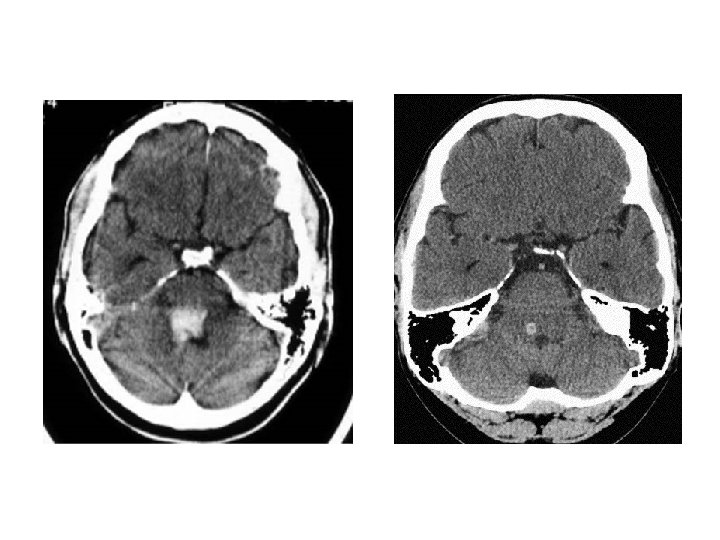

Lobar Hemorrhage • 神經學表現依血塊大小及出血位置不同而 有所不同 • Contralateral hemiparesis or sensory loss, aphasia, neglect, or confusion • Headache is common, disturbance of consciousness is milder

小腦出血 • Dysequilibrium, ataxia, vertigo, nausea, and vomiting. • Brainstem dysfunction (in large hematoma).

腦幹出血 • Rapid development of coma, quadriplegia, conjugate gaze deviation opposite to the lesion or ocular bobbing, and abnormal respiration. • Small pontine hemorrhages occur more frequently than previously thought and produce milder symptoms, such as “pure motor hemiparesis” , “ataxic hemiparesis” or even “Bell’s palsy”.